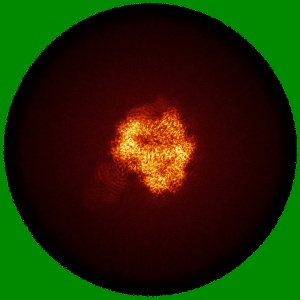

Cryo-EM Structure of HIV-1 BG505DS-SOSIP.664 Env Trimer Bound to DFPH-a.01_10R59P_LC Fab

Sample: BG505 DS-SOSIP DFPH-a.01_10R59P_LC FAB COMPLEX

Fitted models: 9q0w